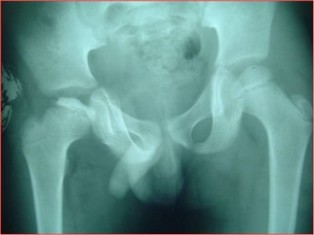

Dislocation of Hip